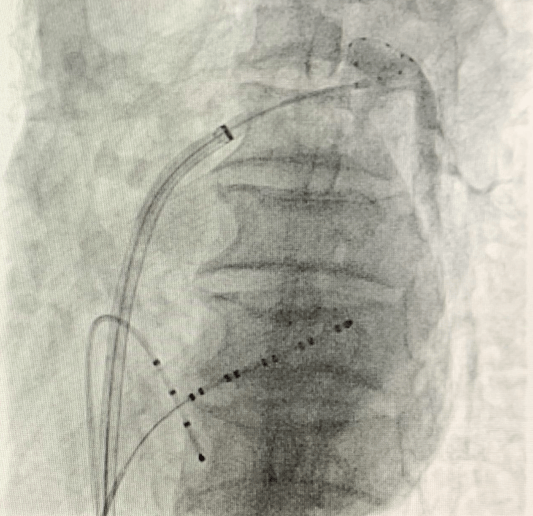

(手術(shù)過程)